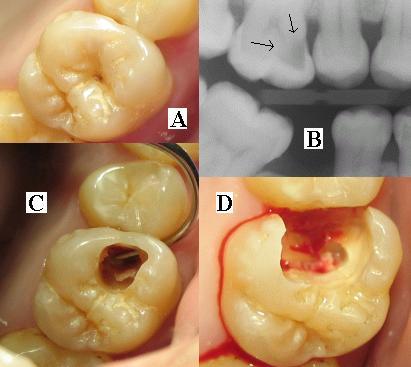

ToothMontage3Японы эрдэмтэн Казуо Ямагашигийн зохион бүтээсэн шинэ төрлийн шүдний бүтээгдэхүүн энэ салбарт хувьсал хийсэн томоохон нээлт боллоо. Их Британийн Daily Telegraph сонинд бичсэнээр тус бүтээгдэхүүн нь маш богино хугацаанд шүдний цооролт бөглөж, пааланг нөхөн сэргээж, өвчин намдаах үйлчилгээтэй гэнэ. Хамгийн гол нь энэ бүхэнд ямар ч шүдний эмчийн тусламж шаардлагагүй юм.

Материалыг гидроксил апатит туршилтаар гаргаж авсан бөгөөд найрлага нь шүдний паалантай төстэй юм байна. Иймээс шүдэнд ан цав гарсан үед ч шууд хэрэглэж болох гэнэ.

Түрхэснээс хойш гурван минутын дараа шүдний хагарч, цоорсон хэсэгтэй нэгдэж бүтэн болдог юм байна. Мөн бактерийн эсрэг бодис агуулдагаараа онцлог болжээ.